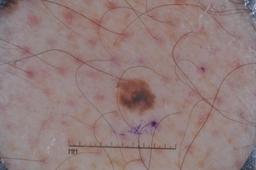

Evaluation set from the ML challenge: SIIM-ISIC Melanoma Classification.